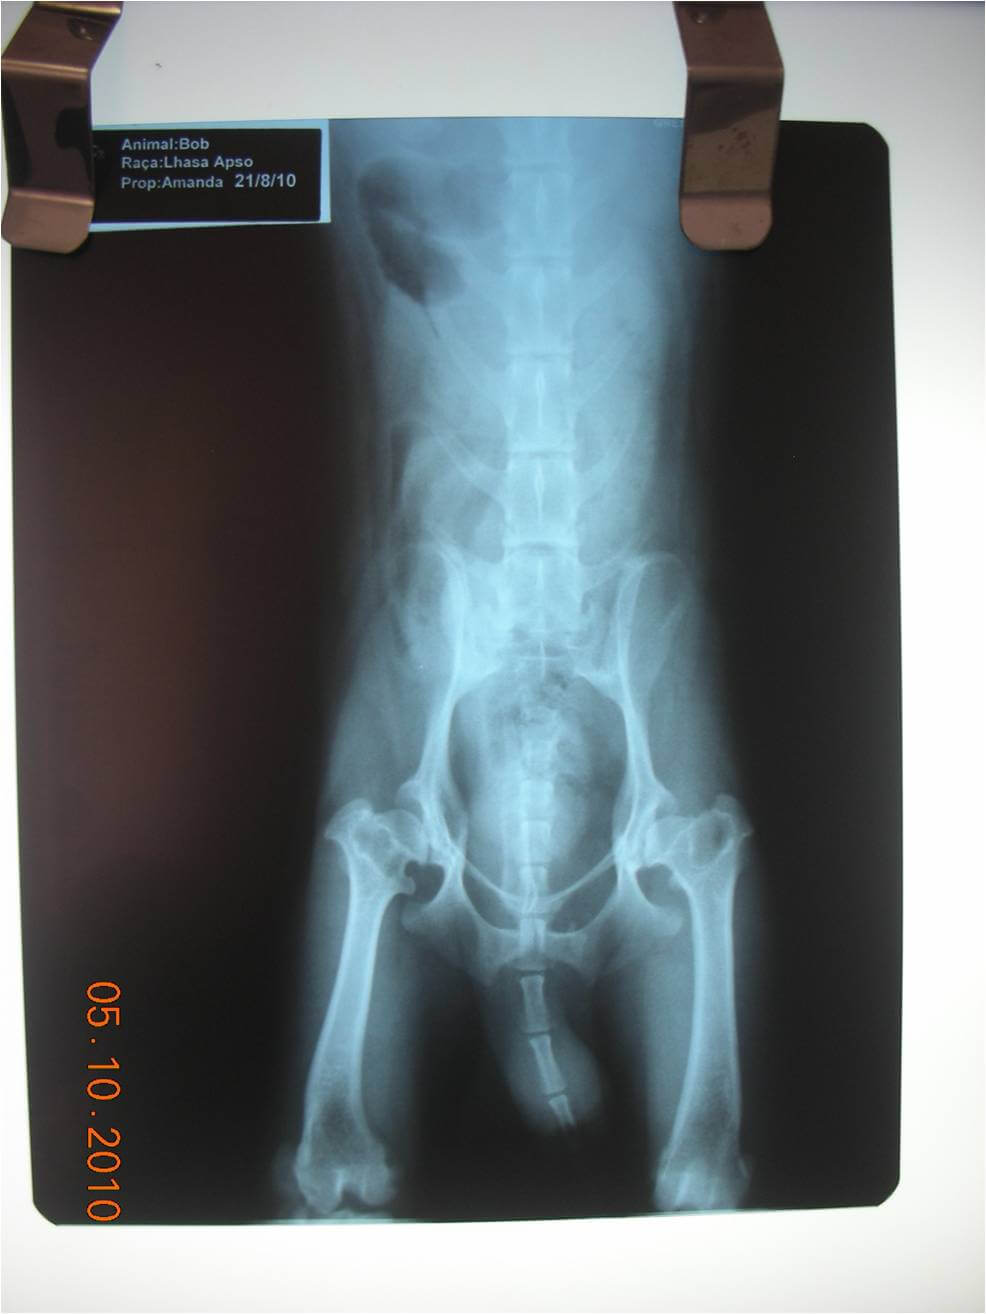

Caso II – Canino, Macho, oito anos, raça Chow Chow. O animal foi atendido em 15/02/2011 apresentando claudição de membro posterior esquerdo, sem histórico de trauma. Durante o exame clinico manifestou sinais de dor no exame local da articulação coxofemoral esquerda. A radiografia (figura 2) revelou subluxação de articulação coxo-femoral esquerda. Neste mesmo dia teve inicio tratamento com o _____________________________________________________________________

complexo Homeopet Displasia®, de acordo com o porte do animal foram administradas 3 borrifadas 3 vezes ao dia. Aos dez dias de tratamento o animal já apresentava diminuição da dor e da claudicação. Em 20/03/2011 (33 dias de tratamento) animal foi reavaliado, constatou-se estar completamente recuperado e caminhando normalmente. Sendo suspenso o tratamento.

Figura 2